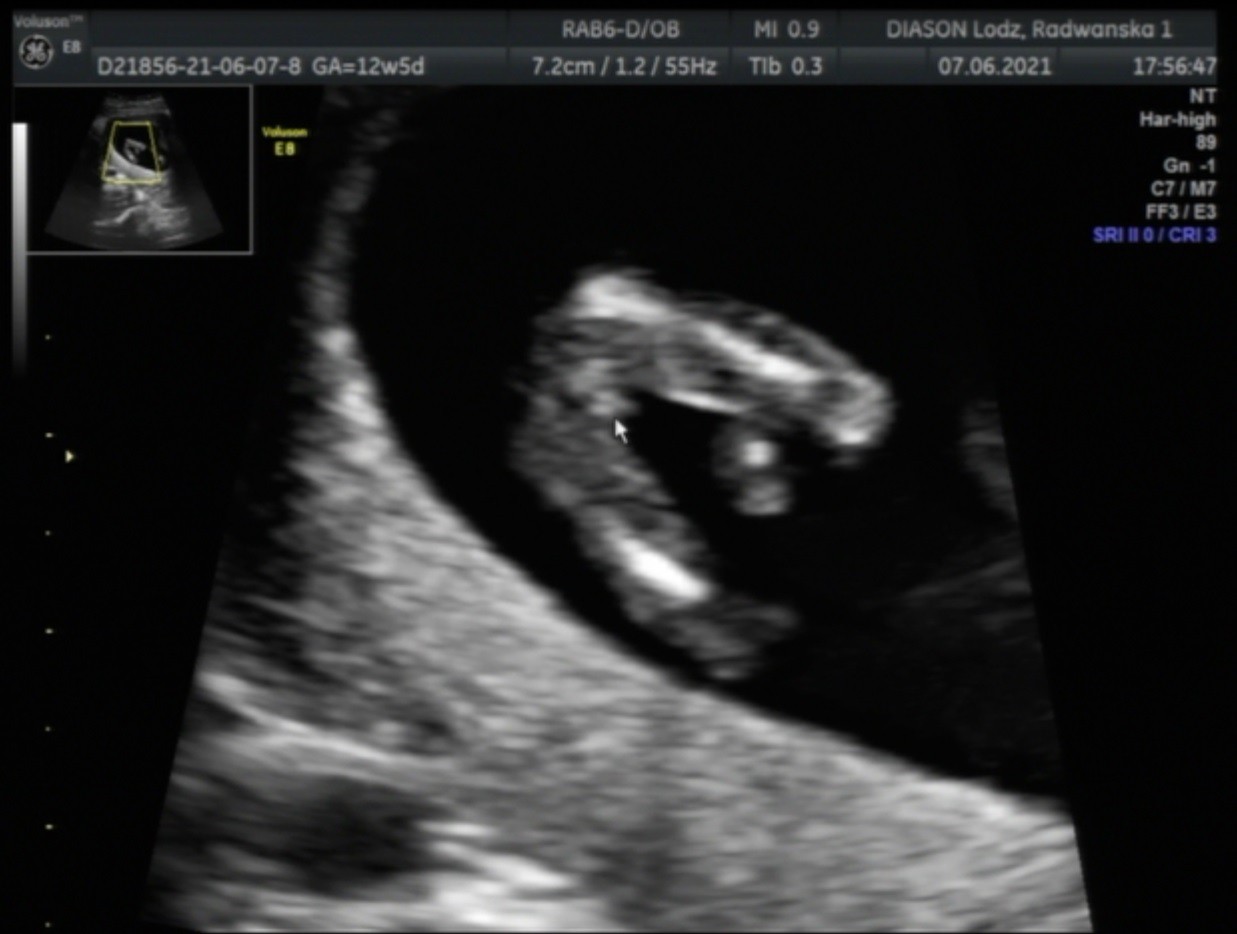

Witam wszystkich😘

Czy mozna cos tu dojrzec? Prosze o ocene🤗

Załączniki

• 162391079995058163150998813343.jpg

162391079995058163150998813343.jpg

1,3 MB · Wyświetleń: 222

• 1623910841266111468245772657511.jpg

1623910841266111468245772657511.jpg

1,3 MB · Wyświetleń: 235